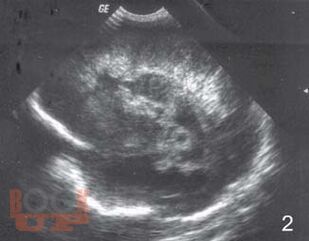

Монография посвящена вопросам ранней диагностики формирования тяжелых структурных постгипоксических изменений мозга у новорожденных детей с помощью определения в крови концентрации нейроспецифических белков, фактора роста сосудов, молекулы клеточной адгезии и маркера апоптоза в раннем периоде постнатальной адаптации. Перед педиатрами и неврологами, занимающимися новорожденными высокого риска всегда встает вопрос: разовьется ли у ребенка внутрижелудочковое кровоизлияние или перивентрикулярная лейкомаляция? Что лежит в основе таких изменений? Результаты, полученные в исследовании, позволили во многом расширить понимание патогенеза постгипоксических изменений головного мозга у новорожденных, а также выделить факторы, которые возможно применять в диагностике патологических процессов в ткани мозга как маркеры. Книга предназначена для детских неврологов, неонатологов, педиатров.